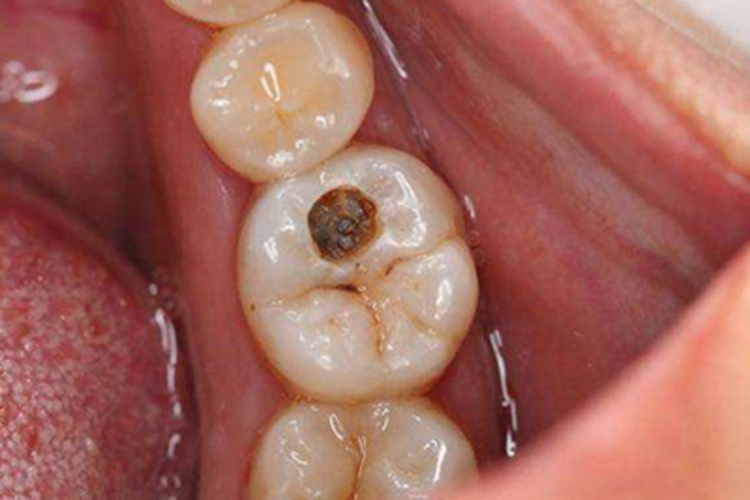

中龋发生后,可见牙齿出现直径3-4mm的圆形缺损,呈窟窿状,里面有褐色的物质,周围牙齿沟纹里有褐色斑点。损害对酸甜刺激敏感,过冷过热饮食也能产生酸痛,冷刺激尤为显著。

中龋牙齿有牙窟窿,是牙齿的硬组织脱钙、软化、破坏而导致。病因较复杂,与细菌、食物中的糖类以及机体对龋病的抵抗力有关。公认的致龋菌有变形链球菌、乳酸杆菌等。